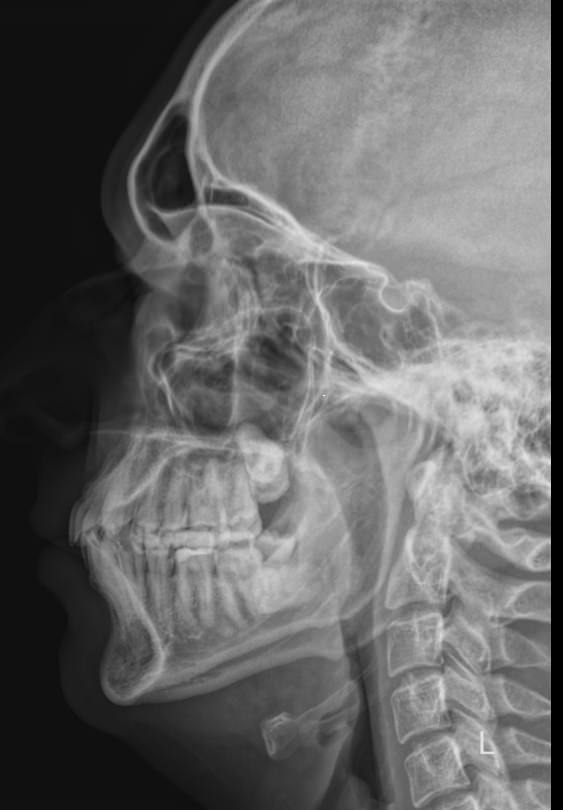

Процедура не требует специфической подготовки. Однако необходимо снять с шеи и головы все металлические предметы: украшения, съемные медицинские гаджеты и предупредить о несъемных. Затем надеть защитный фартук. Далее надо сесть или встать возле пластины детектора и прижать к ней голову, как покажет рентгенолаборант: носом и лбом, носом и подбородком или только подбородком, это зависит от того, какие пазухи подлежат съемке. Так как пазухи парные, то есть расположены симметрично, голову нужно держать ровно, не поворачивая и не отклоняя вправо или влево. Если будет указано в направлении, выполняется несколько снимков в разных проекциях, чтобы были видны разные пазухи.